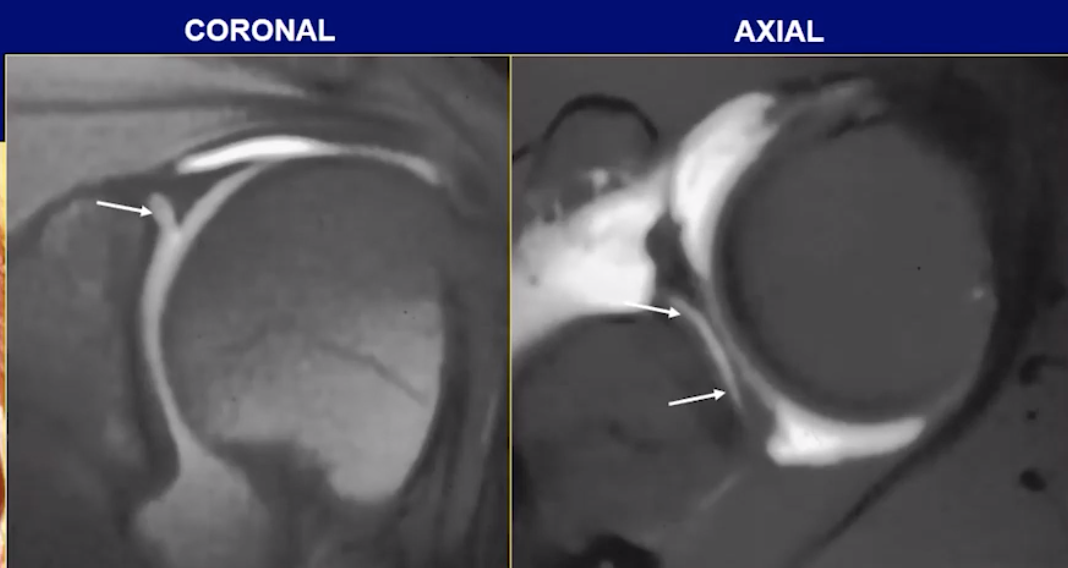

Adhesive Capsulitis

• Capsule thickening and edema

• IGHL ligament thickening, typically >4 mm

• Soft tissue thickening of the rotator cuff interval

• Loss of fat here

• T2 hyperintense & enhance

• Coracohumeral ligament thickening (> 4mm)

• Decreased capsular volume

• Axillary recess appears small

• Basically no fluid around shoulder and the tissues adhere close to the humerus bone

• Unless concurrent other shit the rotator cuff itself and labrum are normal